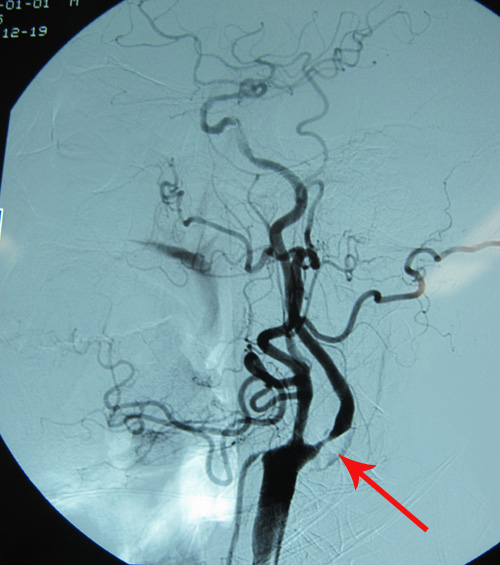

脑动脉造影示:左侧颈内动脉起始部血管狭窄95%

患者23天前无明显诱因突然出现头晕,伴左侧肢体力弱,无明显头痛、恶心、呕吐,无视物旋转、视物模糊、耳鸣、听力下降,无黑曚、晕厥、肢体抽搐。于当地医院就诊行头颅CT检查发现有双侧多发腔隙性脑梗塞,予改善脑循环、降压等药物治疗(具体不详)后症状好转。期间曾行脑动脉造影见左侧颈内动脉起始部血管狭窄95%(未见报告),但介入治疗未成功。1天前无诱因再发头晕不适,伴左侧肢体麻木,偶有黑曚出现,无肢体力弱、 视物旋转,遂至北京市六院就诊。患者自发病来,神清精神可,饮食、睡眠可,大小便基本正常,无明显体重减轻。